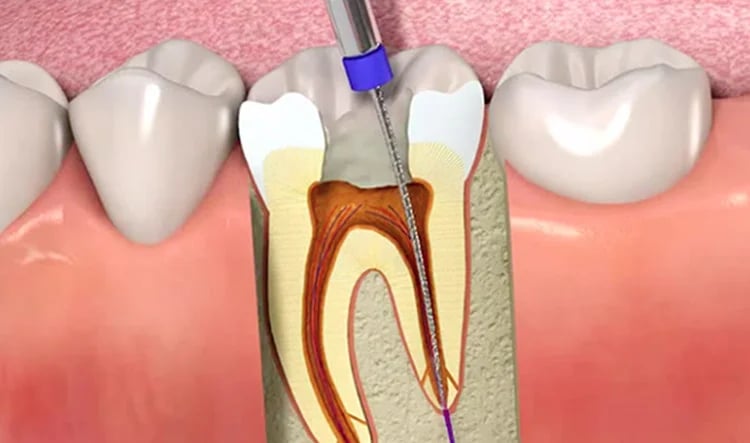

Endodoncias

Es un tratamiento que elimina la infección del nervio dental, se limpia y sella el interior del diente, permitiendo conservar la pieza dental, evitar su extracción y quitando el dolor.